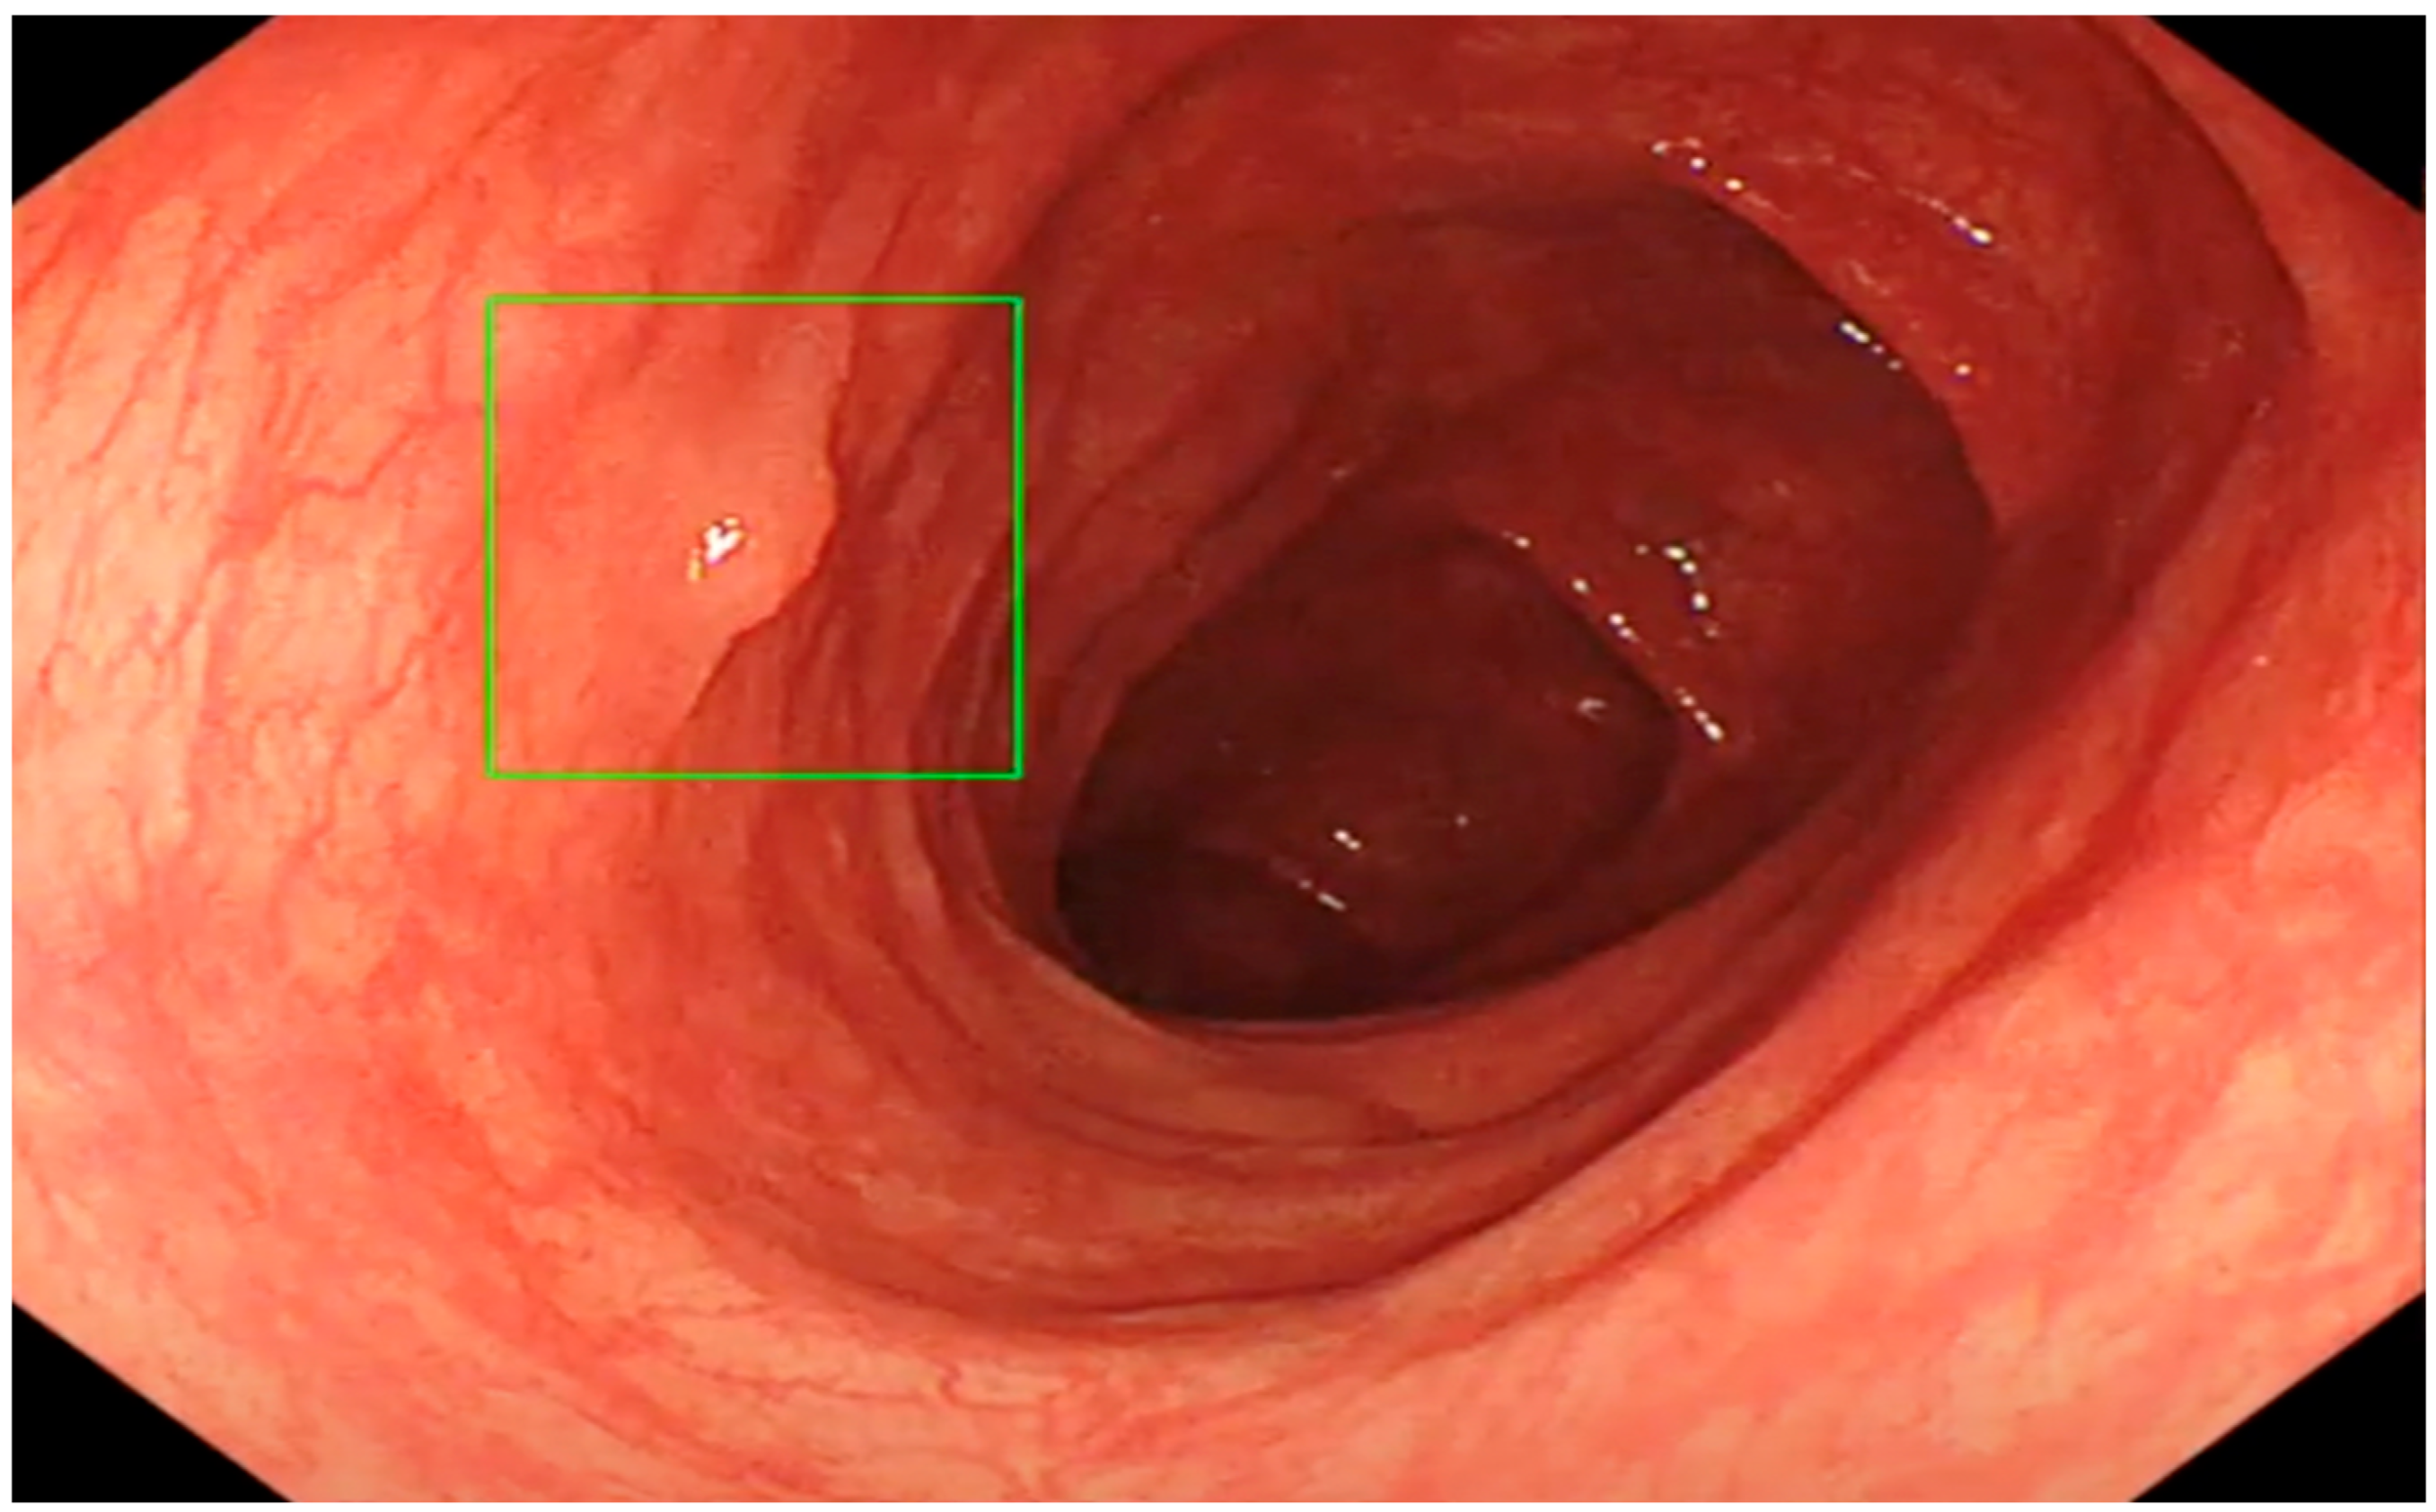

- Misawa, M.; Kudo, S.-E.; Mori, Y.; Cho, T.; Kataoka, S.; Yamauchi, A.; Ogawa, Y.; Maeda, Y.; Takeda, K.; Ichimasa, K.; et al. Artificial Intelligence-Assisted Polyp Detection for Colonoscopy: Initial Experience. Gastroenterology 2018, 154, 2027–2029. [Google Scholar] [CrossRef] [PubMed]

- Klare, P.; Sander, C.; Prinzen, M.; Haller, B.; Nowack, S.; Abdelhafez, M.; Poszler, A.; Brown, H.; Wilhelm, D.; Schmid, R.M.; et al. Automated polyp detection in the colorectum: A prospective study (with videos). Gastrointest. Endosc. 2019, 89, 576–582.e1. [Google Scholar] [CrossRef]

- Alagappan, M. Artificial intelligence in gastrointestinal endoscopy: The future is almost here. World J. Gastrointest. Endosc. 2018, 10, 239–249. [Google Scholar] [CrossRef]